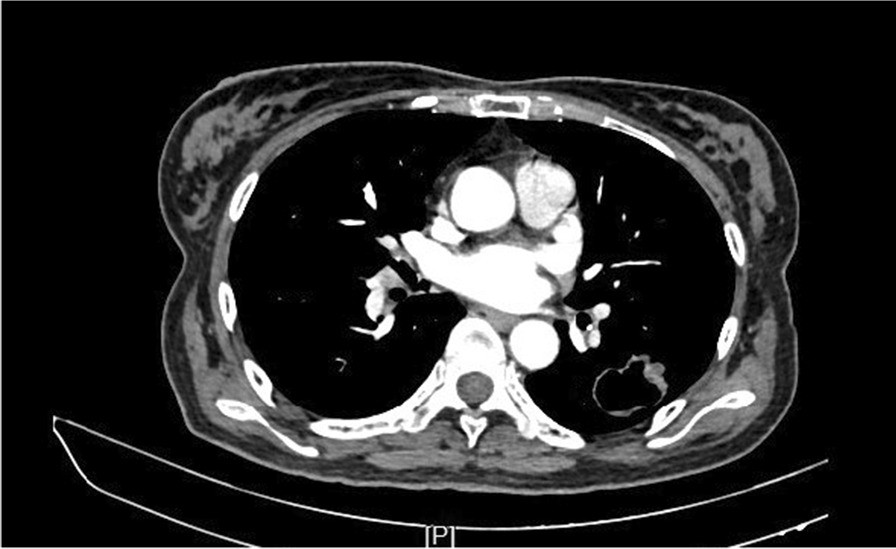

Fig. 6From: Ureteral urothelial carcinoma with squamous cell carcinoma and sarcomatoid carcinoma differentiation: a case reportThere is a mass shadow in the dorsal segment of the left lower lobe, approximately 35 × 24 × 32 mm in size, with lobes, cavities, uneven wall thickness, and enhancementBack to article page